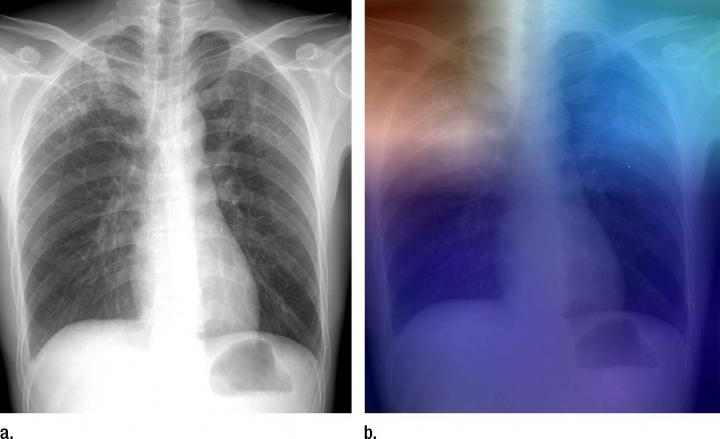

OAK BROOK, Ill. - Researchers are training artificial intelligence models to identify tuberculosis (TB) on chest X-rays, which may help screening and evaluation efforts in TB-prevalent areas with limited access to radiologists, according to a new study appearing online in the journal Radiology .

For the study, Dr. Lakhani and his colleague, Baskaran Sundaram, M.D., obtained 1,007 X-rays of patients with and without active TB. The cases consisted of multiple chest X-ray datasets from the National Institutes of Health, the Belarus Tuberculosis Portal, and TJUH. The datasets were split into training (68.0 percent), validation (17.1 percent), and test (14.9 percent).

The cases were used to train two different DCNN models - AlexNet and GoogLeNet - which learned from TB-positive and TB-negative X-rays. The models' accuracy was tested on 150 cases that were excluded from the training and validation datasets.

The best performing artificial intelligence model was a combination of the AlexNet and GoogLeNet, with a net accuracy of 96 percent.